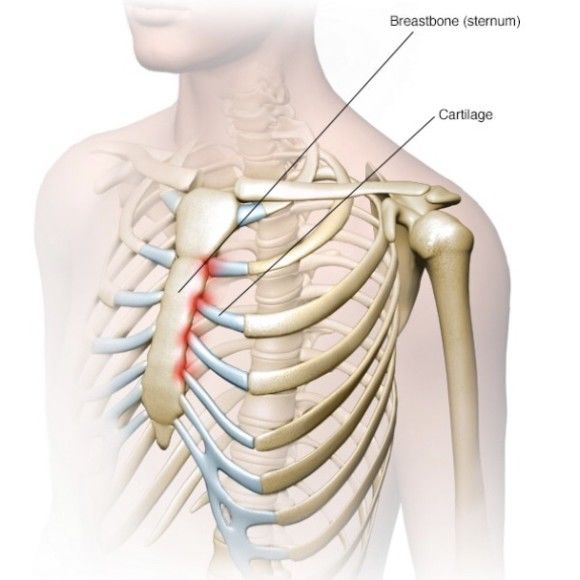

늑연골염

늑연골염은 갈비뼈와 흉골을 연결하는 연골 부위에 염증이 생겨 발생하는 상태입니다. 염증은 주로 가슴 중앙이나 양쪽 늑골 앞쪽에서 통증을 일으키며, 깊게 숨을 쉬거나 기침할 때 통증이 더욱 두드러지게 나타납니다. 통증은 날카롭거나 쑤시는 느낌으로 표현되며, 가슴 통증과 혼동되는 경우도 많습니다.